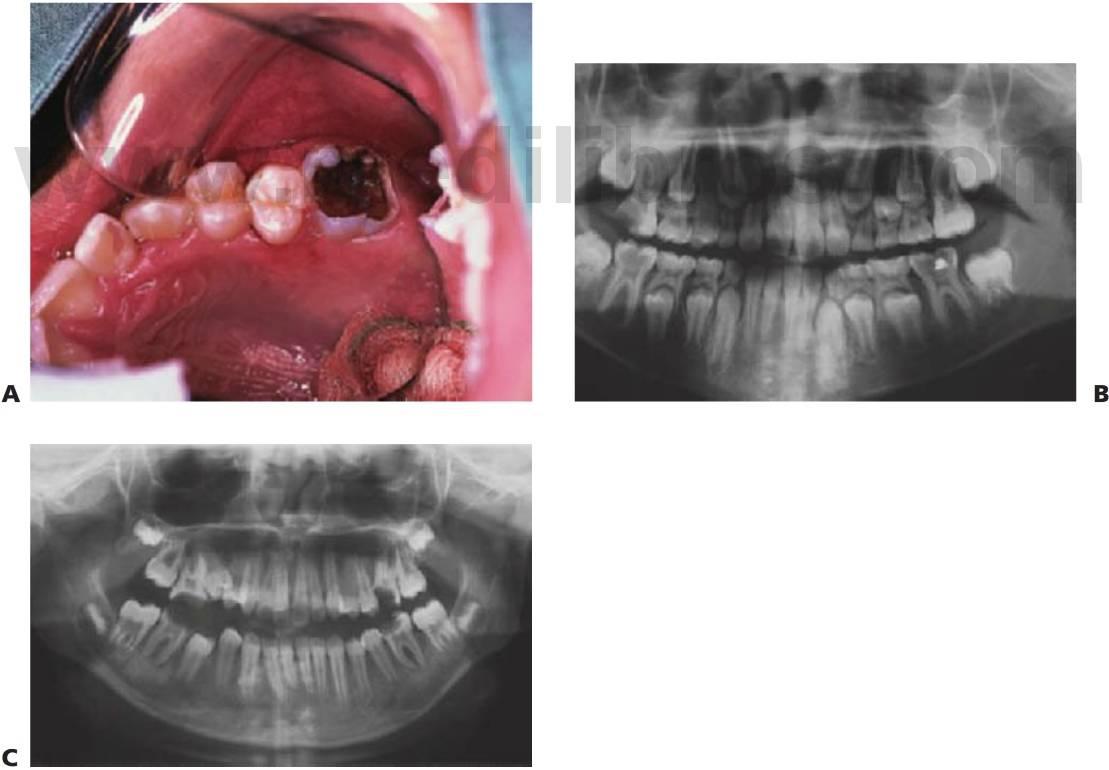

- Dientes permanentes ectópicos (fig. 6.2).

- Una fractura del reborde marginal en un diente temporal sugiere la afectación pulpar cariosa en contacto con una caries puntual (fig. 6.4A).

- La fractura de los rebordes triangulares oclusales o la socavación cariosa de las cúspides en las caries de fosas y fisuras también sugiere afectación cariosa (fig. 6.4B).

Por desgracia, el aspecto externo de la lesión cariosa puede llevar a confusión en algunos casos (fig. 6.5). Los síntomas persistentes que aparecen poco después de colocar una restauración indican afectación pulpar y la falta de sellado coronal desembocará también, inevitablemente, en una lesión pulpar. El examen radiográfico se revela esencial para complementar los hallazgos clínicos y aumentar la exactitud del diagnóstico.

La inflamación alveolar, sobre todo la que afecta a la reflexión vestibular y la hinchazón facial, la decoloración coronal y la presencia de un seno indican una necrosis pulpar y la formación de un absceso (fig. 6.3B).